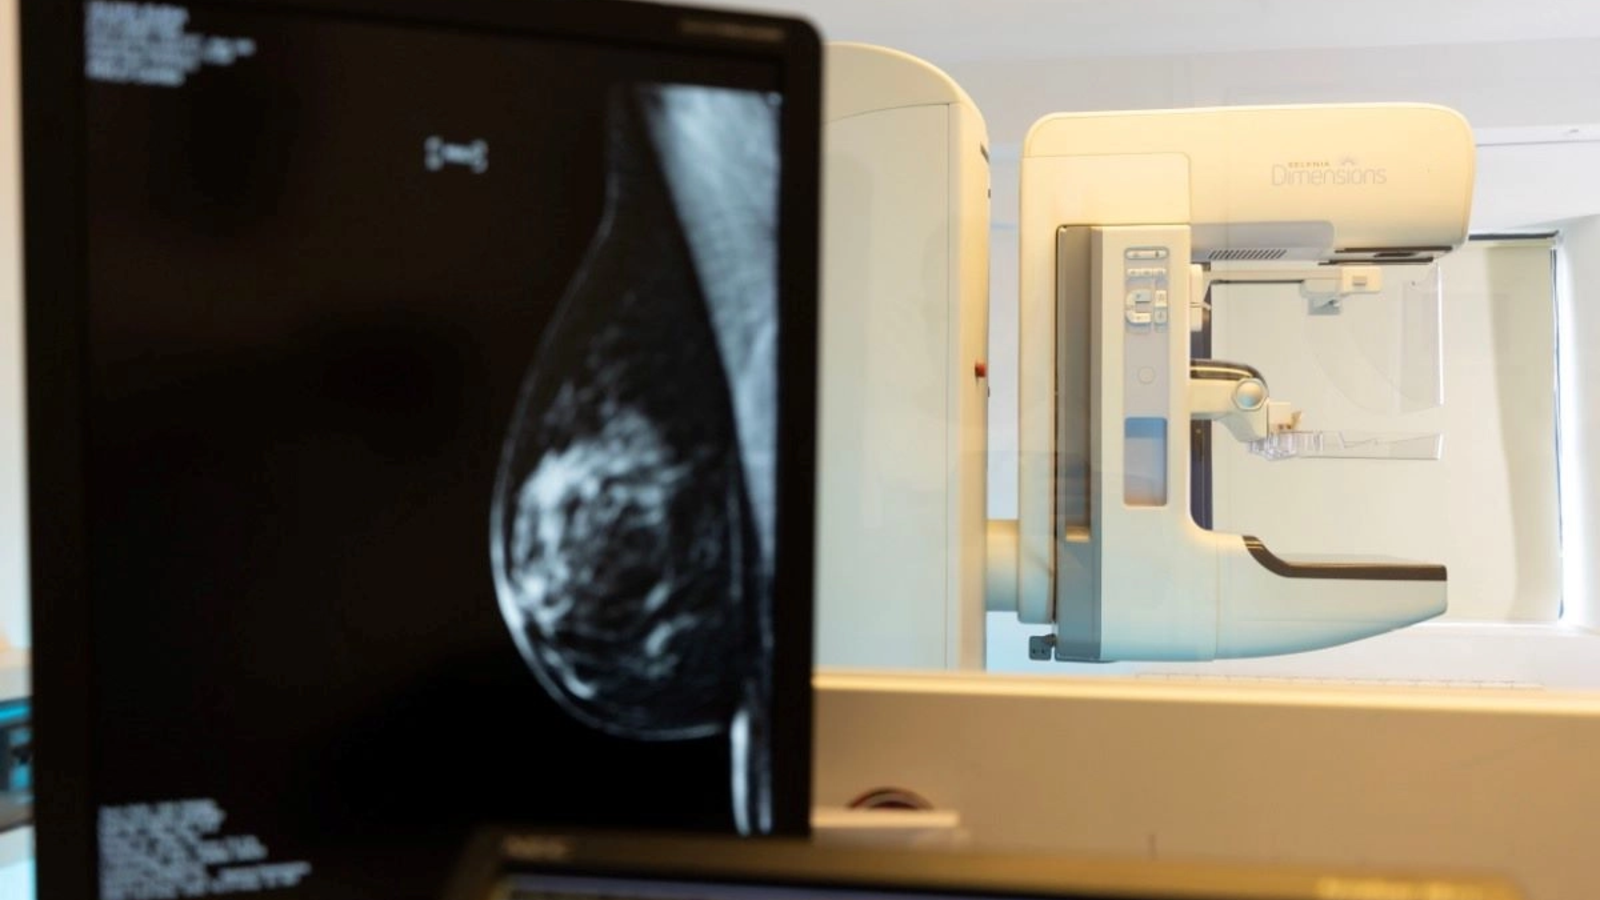

Cea mai performantă investigație de screening și diagnostic pentru cancerul de sân este mamografia digitală cu tomosinteză. Spre deosebire de mamografia clasică, aceasta creează o imagine tridimensională a sânului, astfel că pot fi identificate leziuni foarte mici, chiar și la femeile care au sânul mai dens.

SANADOR asigură servicii medicale complete pentru screeningul, diagnosticul și tratamentul cancerului mamar. În Clinica SANADOR Victoriei Corp A, pacientele au acces la mamografie cu tomosinteză efectuată cu Selenia Dimensions 3D Hologic, unul dintre cele mai avansate echipamente de acest fel disponibile în prezent. De asemenea, la SANADOR pot fi realizate ecografii mamare performante, RMN mamar și biopsie mamară.